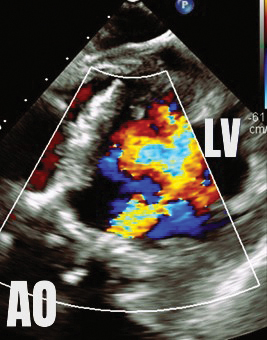

The case is reviewed by a multidisciplinary cardiology team consisting of a structural interventional cardiologist, a cardiothoracic surgeon, and a noninvasive cardiologist with expertise in advanced cardiac imaging. The location and dimensions of the paravalvular leak are deemed suitable for transcatheter closure using a nitinol vascular plug (see Fig. 2).

Under general anesthesia and with transesophageal echocardiography guidance, the defect is successfully crossed using a hydrophilic guidewire introduced via the right radial artery. A 6-French guide catheter is advanced across the defect, and a 12-mm nitinol vascular plug is deployed. Prior to device release, selective coronary angiography of the left main coronary artery is performed to confirm vessel patency (see Fig. 3).

Post-deployment TEE demonstrates complete elimination of the paravalvular leak.